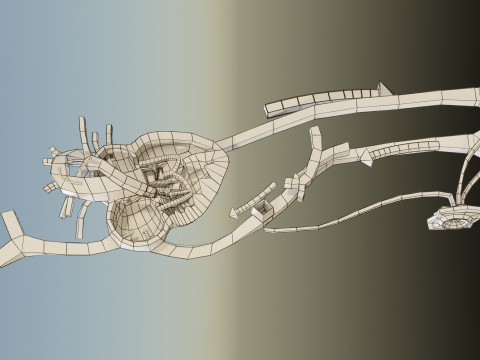

The model meshes include adult circulation versus circulation in Tetralogy of Fallot (TAF), arrow labels and text labels. The blood flow in a patient with Tetralogy of Fallot is outlined in this model. To contrast it to normal blood circulation a separate model of normal circulation is included. The Tetralogy of Fallot (OVER RIDING OF AORTA, PUL STENOSIS, VENTRICULAR SEPTAL DEFECT, RIGHT VENTRICULAR HYPERTROPHY), fossa, ligament teres , venosus, and arteriosus are duly depicted with proper labelling and blood flow directional arrows. Excellent model for teaching, demonstration and knowlegde of human body. The models include both procedural and image textures blend files separately. The texture file include diffuse, roughness and normal png and jpeg based on non overlapping UV maps.